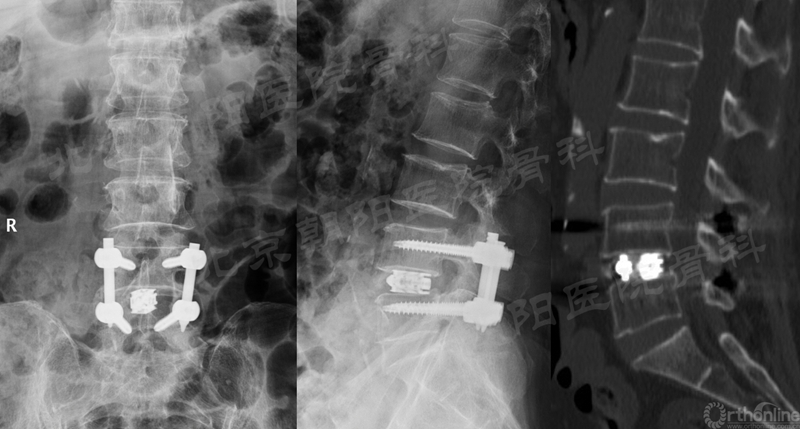

在经历15例UBE减压手术的学习曲线后,本团队进行了UBE腰椎减压融合术:#16例UBE,L4/5 LSS。

术后X线片与CT(矢状面)

术前、术后MRI及CT(轴位)